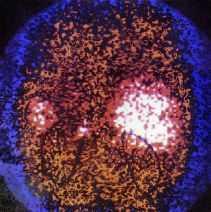

Una paciente de 46años, con historia de hipertensión arterial, acude alhospital por dolor subxifoideo opresivo, náuseas y disneaprogresiva, que hace necesaria su intubación yconexión a ventilación mecánica. Elelectrocardiograma (ECG) de ingreso muestra ritmo sinusal y datosde hipertrofia ventricular sin otros datos de interés, y uncorazón ecocardiográficamente normal. Durante losprimeros días presenta tendencia a la hipertensión.Evoluciona posteriormente con inestabilidad hemodinámica,por lo que ante la sospecha de un feocromocitoma se determinanmetanefrinas y ácido vanil mandélico en orina de 24horas, con valores respectivos de 10 mg (r.n. hasta 1 mg/24 h) y 18mg (r.n. hasta 5 mg/ 24 h). En la tomografía axialcomputarizada (TAC) abdominal (fig. 1) se observa unatumoración suprarrenal izquierda de 3 cm compatible confeocromocitoma; y la gammagrafía con131metaiodobencilguanidina (fig. 2) detecta un foco deactividad aumentada en área craneomedial delriñón izquierdo. La paciente fue tratada con alfabetabloqueantes y adrenalectomía evolucionandofavorablemente.